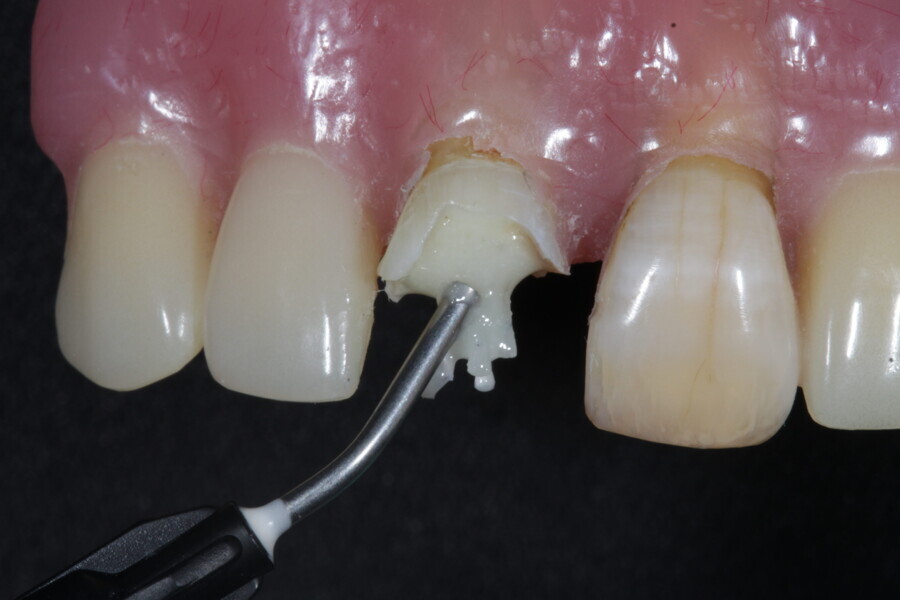

1. functional and aesthetic reconstruction of a maxillary anterior tooth using fibre-reinforced flexible micro-posts after endodontic treatment (Figs. 3–20);

Example 1—showing functional and aesthetic reconstruction of a maxillary anterior tooth using fibre-reinforced flexible micro-posts after endodontic treatment.